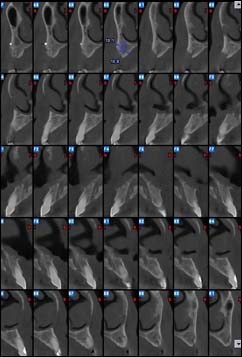

Reconstruction coronale